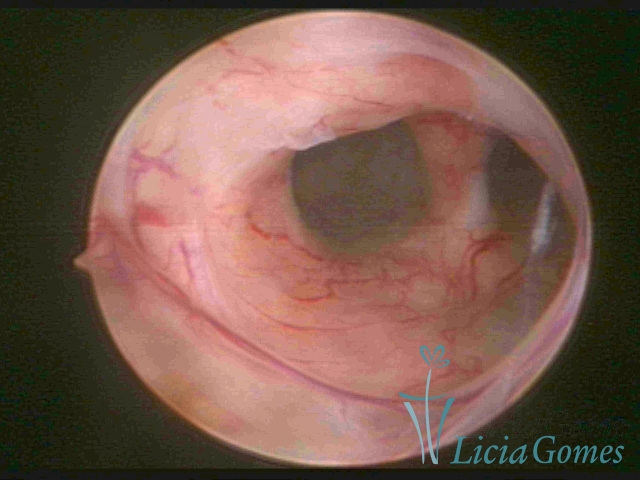

Septate uterus